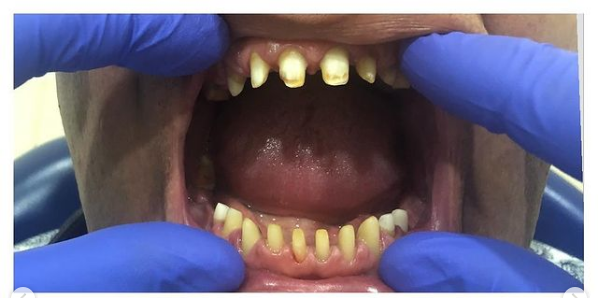

Установка коронки из диоксида циркония

Доктор: Базаян Арсен Андреевич

Женщина, 40 лет, верхняя челюсть протезирована ранее (мостовидный протез из диоксида циркония), обратилась в клинику с целью улучшения эстетики фронтального отдела (нижняя челюсть). - Проведено депульпирование зубов перед протезированием. - Следующим этапом зубы были препарированы под коронки из диоксида циркония, сняты оттиски, зафиксированы временные коронки (прямой метод) - Фиксация постоянных коронок